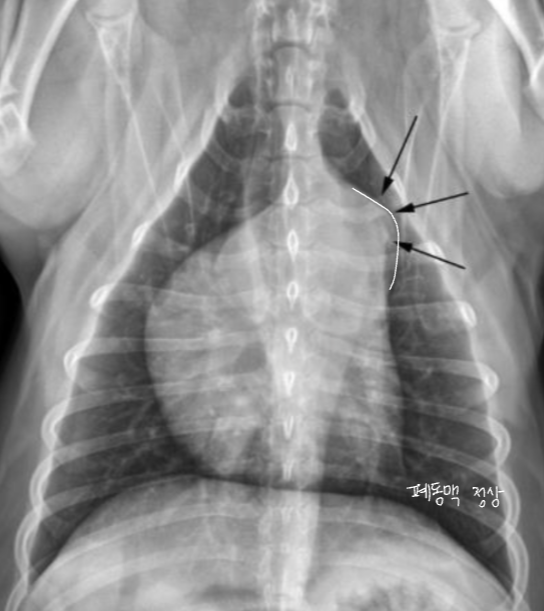

Pulmonic stenosis, Pulmonic hypertension

| PS | PH (โ HW) | |

|---|---|---|

| ํ๋๋งฅ ํ์ฐฉ์ฆ. ํ๋ง์ด ์ข์์ง๋ ์งํ. ์ข์์ง ๋ถ์์ ๋ค์ ๋ถ๋ถ์ด ํ๋ฅ๋ก ์ธํด ์๊ทน๋์ด ํ์ฅ. ํ์ก์ ๋ด๋ณด๋ด๊ธฐ ์ํด ์ฐ์ฌ์ค ์๋ ฅ ์ฆ๊ฐ, ๋น๋. ์ฐ์ฌ๋ฐฉ โ ์ฐ์ฌ์ค๋ก์ ํ๋ฅ ์ฅ์ ๋ก ์ธํด ์ฐ์ฌ๋ฐฉ๋ ๋น๋. | ์ฃผ ์์ธ์ ์ฌ์ฅ์ฌ์์ถฉ. - ๋ง๋จ ํ๋๋งฅ์ด ๋๊บผ์์ง๊ณ , ๊ตฌ๋ถ๊ตฌ๋ถํด์ง. - ํ๋๋งฅ ์๋ ฅ ์์น โ RV hypertrophy โ RA enlargement | |

| Radiographic sign - mPA bulging (1์ ๋ฐฉํฅ) : Reversed D - RVE, RAE - post-stenotic dilation : ๊ตญ์์ ์ผ๋ก ๋ฐ์, ๋ง๋จ ํ๊ด์ ์ ์ - ํ๋๋งฅ์ ์ ์์ธ ๊ฒ์ด ํน์ง (PH๋ ํ๋๋งฅ ์ปค์ง) | Radiographic sign - mPA ํ์ฅ โ Reversed D sign - RV hypertrophy - Pulmonary artery enlargement, tortuosity - RCHF์์์ฒ๋ผ Hepatomegaly, ascites, pleural effusion | |

![]() | ![]() | |

![]() | ![]() |